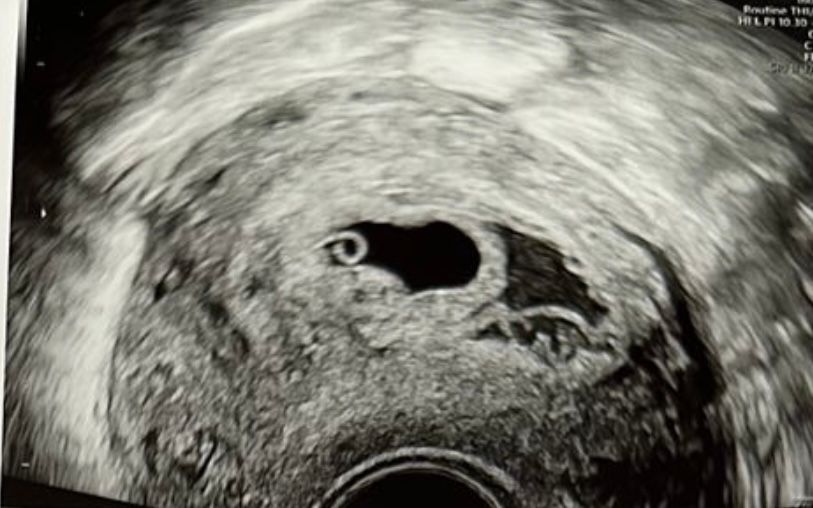

Кристина, да черт ее знает.. большая, с плодное яйцо размером. Но выделений не было. Только поясница всю неделю болела сильно. На предыдущем узи не было отслоек. Вот то что справа я так понимаю отслойка Изображение